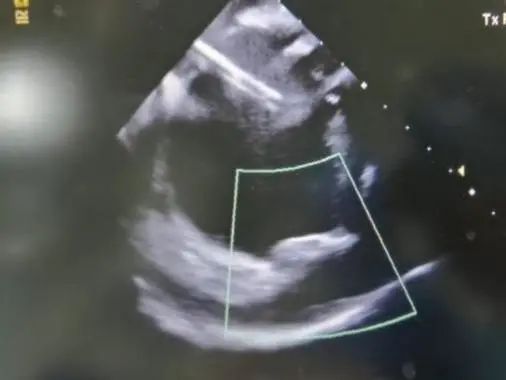

在ICE指导和DSA影像下,沿猪尾将鞘管推送至目标位置,撤猪尾后,选择33mm封堵器植入,整个封堵器展开的过程,退鞘动作慢而稳,封堵器一次展开后即在预期封堵位置区间,DSA下通过肝位(RAO30 CAU20)和足位(RAO1 CAU20)造影确认其位置,结合ICE下显示,封堵器植入到了非常完美的位置。完全符合成功的标准,即PASS 原则:P:位置准确;A:固定良好;S:大小合适,压缩比15%;S:封堵完全,无残余分流;完美释放,手术顺利结束(图5,6)。

图6. ICE下评估PASS原则,封堵器释放